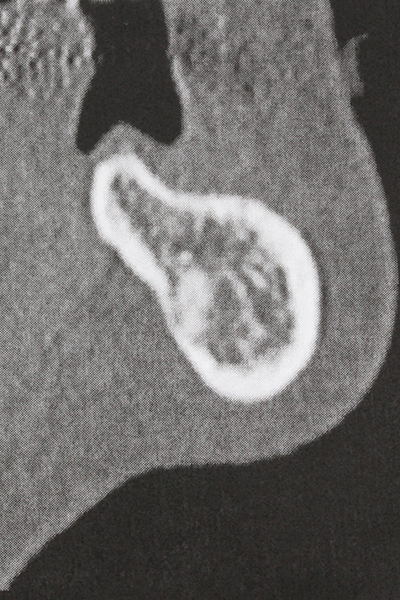

Както е показано в миналото, всяка костна хирургия представлява възможна индикация за пиезохирургия. По този начин, за препарацията на подвижни сегменти в остеогенеза (Фиг. 23-25) и остеотомия се използват специални накрайници, без да се застрашава снабдяването с кръв в кресталната зона, което е от съществено значение за успеха и на двете техники (Gonzalez-Garcia, Diniz-Freitas et al. 2008).